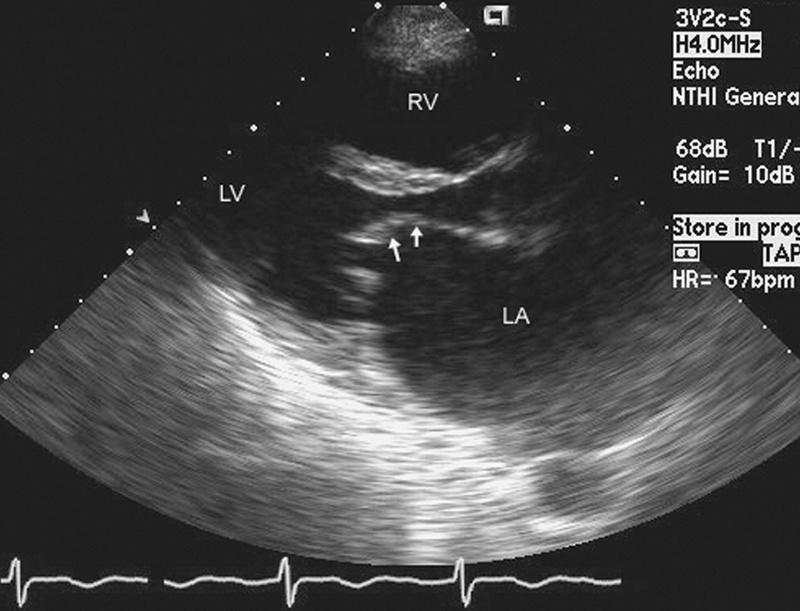

فحوصات تشخيصية لبعض امراض القلب والشرايين التاجية